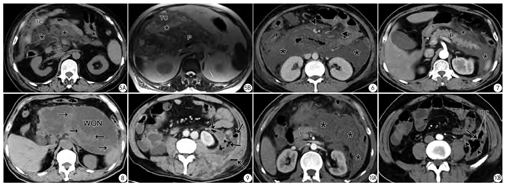

新亚特兰大共识对AP的4种局部液体积聚进行了重新命名,值得注意的是,患者首次症状发作至CT/MRI检查的时间需弄清楚,这对液性积聚的命名很重要。通常,APFC(图7)或ANC(图1)发病4周后(含4周)就需报告为PP或WON(图8)。在描述WON的内容物特征时,需观察固体状坏死物占整个液性积聚的百分比,这对患者治疗方式的选择有价值。Rana等[4]通过对43例有症状的WON行内镜超声引导下治疗,WON坏死碎片占比<10%时,仅需一次内镜引流;而坏死碎片占比达10%~40%时需至少两次内镜引流方能治愈;当实性坏死碎片占比>40%时,要么需在超声内镜下行坏死组织清除术、要么需行外科手术坏死组织清除术。即随着实性碎片量的增多,经超声内镜操作的次数也明显增加[4]。

因为胰周液性积聚合并感染会导致AP患者的死亡率明显增高[1],故当APFC/ANC或PP/WON内出现气体影时,需在CT/MRI报告中予以描述并提示为感染性积聚(图9)。此外,胰周长期的液性积聚可能会腐蚀邻近的消化管而继发肠瘘,故需报告可能并发肠瘘的肠管段(图10)。合并有肠瘘的患者是外科手术的适应症。

胰腺/胰周的包裹性液性积聚若累及胰腺的全程(透壁性坏死),常可使主胰管破裂中断(图11),继发所谓的“主胰管中断综合征”。出现此类并发症也常常需要外科手术处理。

尽管慢性胰腺炎和胰腺癌是引起胰源性门脉高压的主要原因,但AP相关的胰源性门脉高压需要重视(图12)。笔者对633例连续AP患者行MRI检查发现胰源性门脉高压发病率为3.3%(21/633);且在轻度、中度、重度AP中的发病率逐渐增加[10]。此种并发症可能与患者后期消化道出血有关,故而在报告中予以描述。